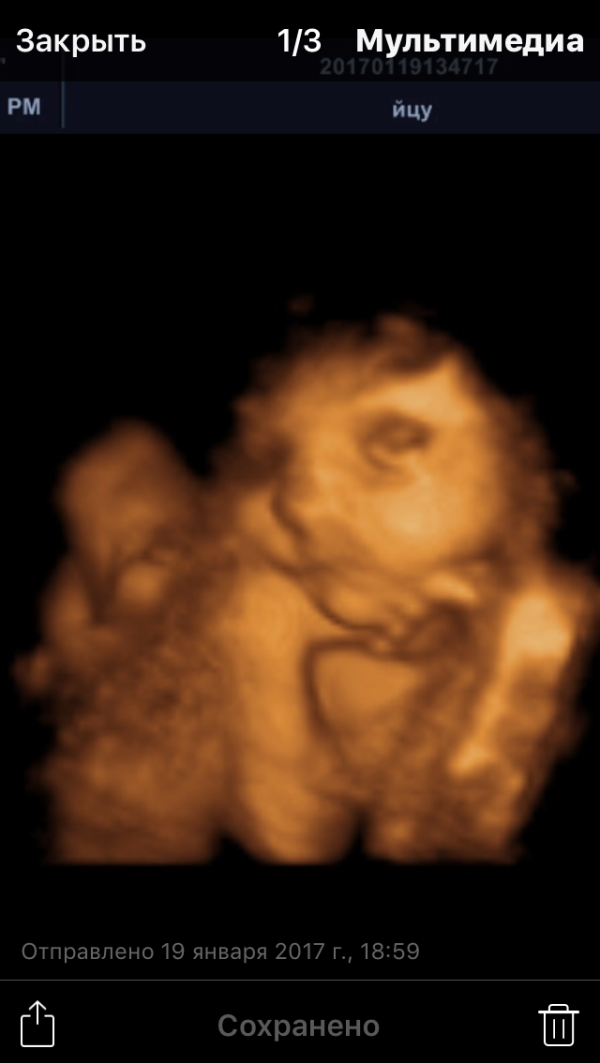

Девочки, сегодня были на 4Д УЗИ! Столько непередаваемых эмоций... просто не расскажешь словами)❤ С сынишкой все хорошо, весим уже 1300 кг, подбородочек ручонками подпираем) но вот шейка уже укоротилась до 2,2 см😔 Так что укладываться спать будем теперь с Утрожестаном, а потом возможно в итоге не избежать нам "колечка"...😔 Как то так....